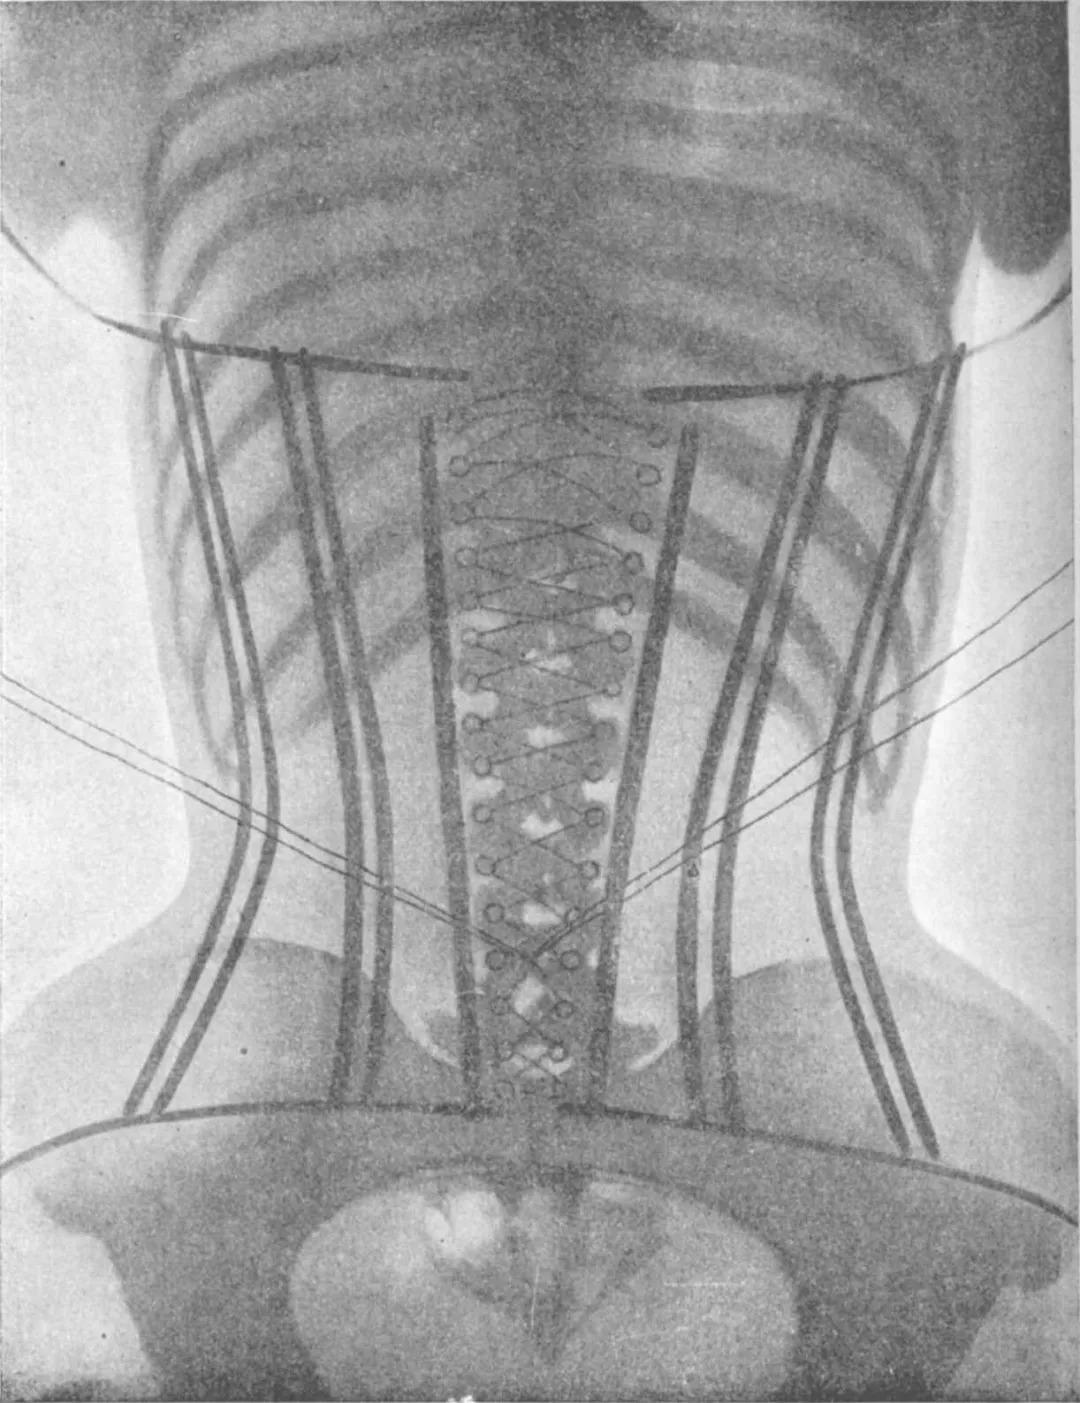

历史上束腰第一次在潮流中逐渐暗淡,就归功于每年数篇讨论束腰不利于内脏健康的论文。它会压迫内脏,引起胃酸返流。

束腰对内脏的压迫;图/Valencian Museum of Ethnology

尽管现代束腰——塑形内衣通过各种术语试图改变这种印象,比如声称使用了新型材料和技术等,医学对塑形内衣造成生理和心理危害的警告依然存在,神经痛、消化困难、静脉曲张、血栓等病症名列塑形内衣生理风险的头几位。

当然,现代塑形内衣在广告策略上都会反复使用“不要太紧,适当使用,配合运动使用”这些听起来温和健康的说法。然而,如果贴身牛仔裤已经在医生警告的有可能损害健康的范围内,我很难相信穿塑形内衣可以宽松到不对身体产生过度的挤压。

英国布里斯托理疗诊所的主任理查德.布里克内尔认为,穿塑形内衣可导致换气过度综合症,恐慌发作和压力性尿失禁。过紧的衣服,装饰品也会导致同样的问题,如腰带。